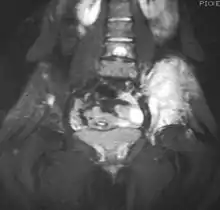

Magnetic resonance imaging (MRI) should be routinely used in the work-up of malignant tumors. It will show the full bony and soft tissue extent and relate the tumor to other nearby anatomic structures (e.g. vessels). Gadolinium contrast is not necessary as it does not give additional information over noncontrast studies, though some current researchers argue that dynamic, contrast-enhanced MRI may help determine the amount of necrosis within the tumor, thus help in determining response to treatment prior to surgery.

Computed axial tomography (CT) can also be used to define the extraosseous extent of the tumor, especially in the skull, spine, ribs, and pelvis. Both CT and MRI can be used to follow response to radiation and/or chemotherapy. Bone scintigraphy can also be used to follow tumor response to therapy.